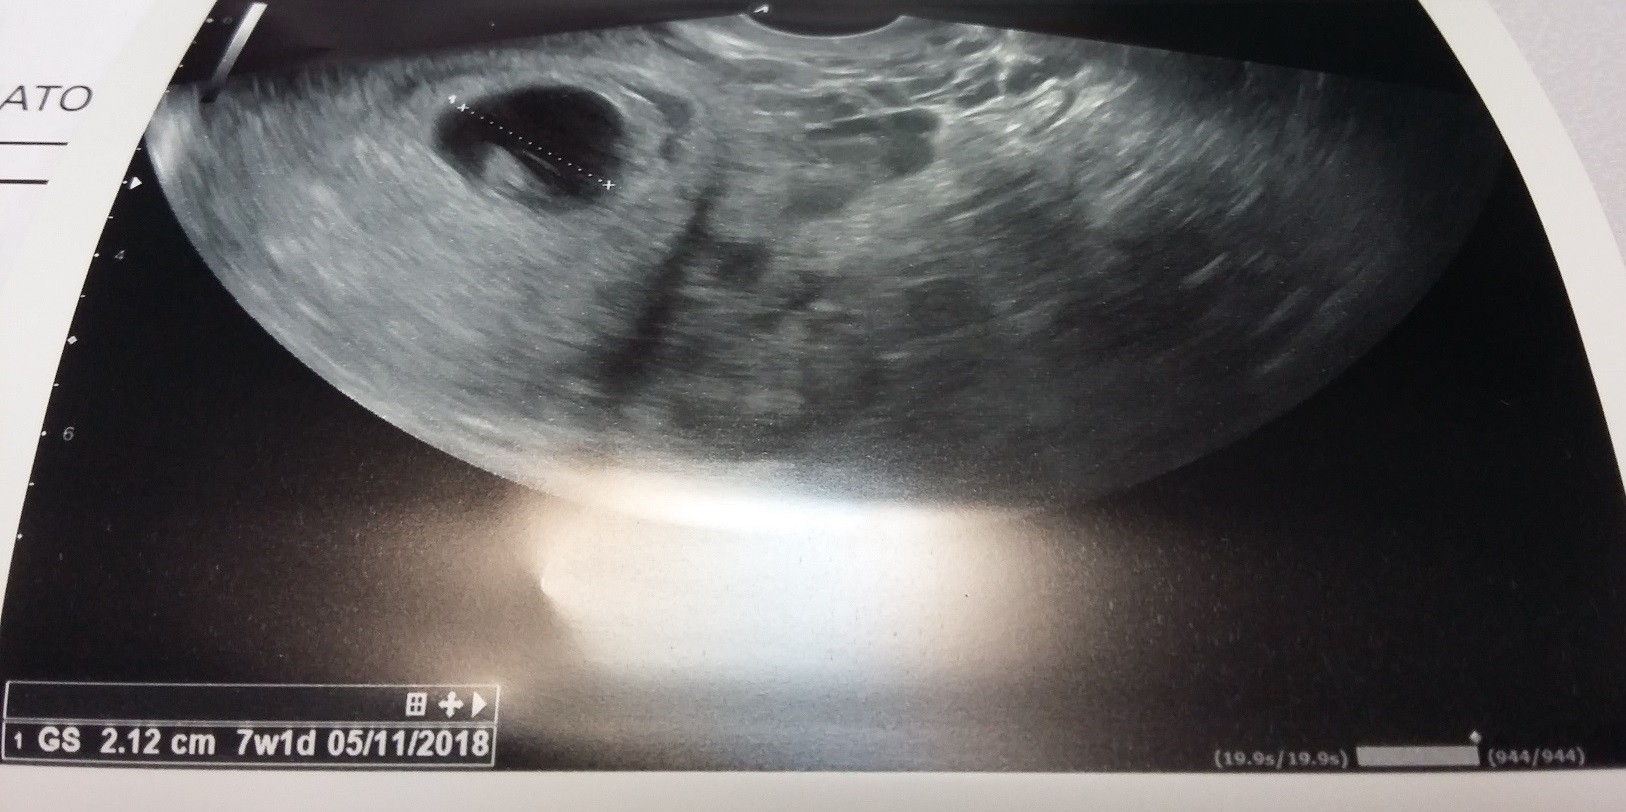

Ja po wizycie. Wizyta okropna. Dobrze, że idę tam tylko raz. Nie dała mi zdjęcia z usg, powiedziałam że maż w domu z córką i czekają i będą się cieszyć, to powiedziała, że to jest małe by się z tego cieszyć. Pozwoliła mi zrobić tylko zdjęcie z usg, które miała do dokumentacji. Widziała serduszko, ale mi nie puściła, choć ją prosiłam, też stwierdziła, że dziecko jest małe i posłucham na następnej wizycie. Jak się dopytywałam czy serduszko jest i czy wszystko w porządku to powiedziała, że tak. Mało się tam nie rozpłakałam. Zazdroszczę dziewczyny, ja usłyszę serduszko dopiero w 10 tygodniu za dwa tygodnie